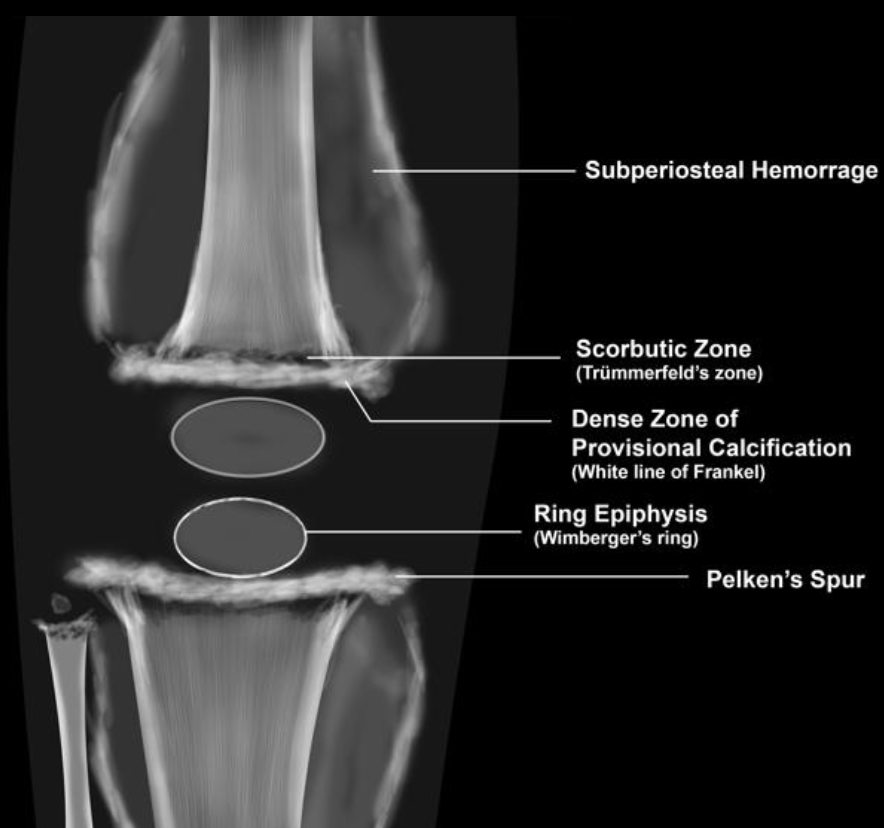

Scurvy

• Wimberger Ring sign

• Dense calcification surrounding the developing epiphysis

• Subperiosteal hemorrhage

• Generalized osteopenia

• Hemarthrosis

• Frankl line = dense line of calcification

• Trummerfield zone = lucent zone deep to Frankl line

• Pelkan spur = metaphyseal spur from healing microfractures